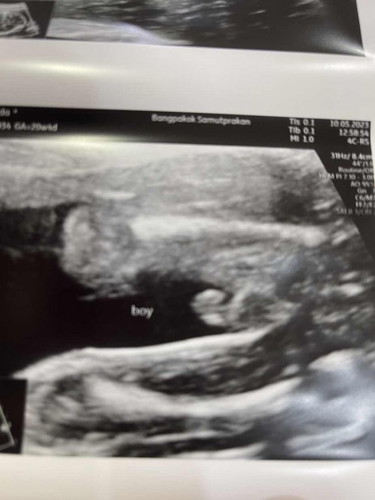

แบบนี้ผู้ชายชัวใช่มั๊ยคะ จะไม่เซอร์ไพรส์ตอนคลอดใช่มั๊ยคะ😁

เป็นแท่งและ2ฟองเลยค่ะแม่ 🤣

ชัดเจนค่ะแม่